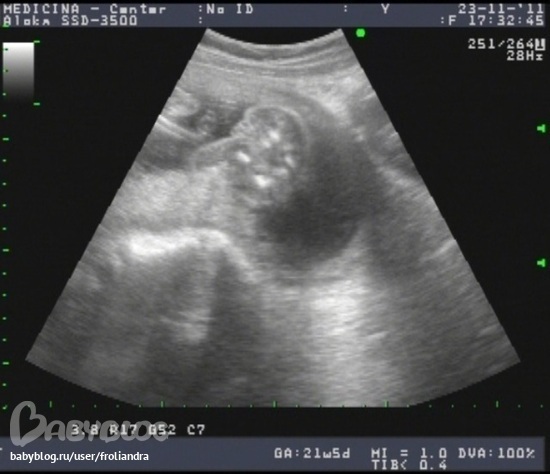

Вот фотка с узи для определния пола :) - ракурс: попа :))

показали два "холмика" - сказали - половые губы. Первая реакция - шок - как я мужу скажу, он же сына ждет (а вдруг он малышку любить больше не будет?! а меня?!), и все вокруг мне твердят что это мальчишка :))) И я в это верила. С момента зачатия была уверена что М., потом меня переклинило на Д., потом опять на М., и на УЗИ я ждала увидеть М. :) Потом прошло, слушаю что все у нас хорошо и развитие соответствует сроку полностью, и все показатели в норме - замечательно! Поуспокоилась - главное что меня беспокоило - это постоянно выписываемые витамины для плаценты - оказалось все нормально - 23 мм! И околоплодные воды в норме. Вес плода уже 416 г!!! :) Только два узла нашли на матке :(

Может быть ошибка про пол?! Пишут в нете: вся проблема ошибок в этом и состоит. Губы у девочек большие до рождения, а у мальчиков яички еще не опустились, так же и писюнчик и клитор, поэтому очень легко все перепутать, все очень похоже.